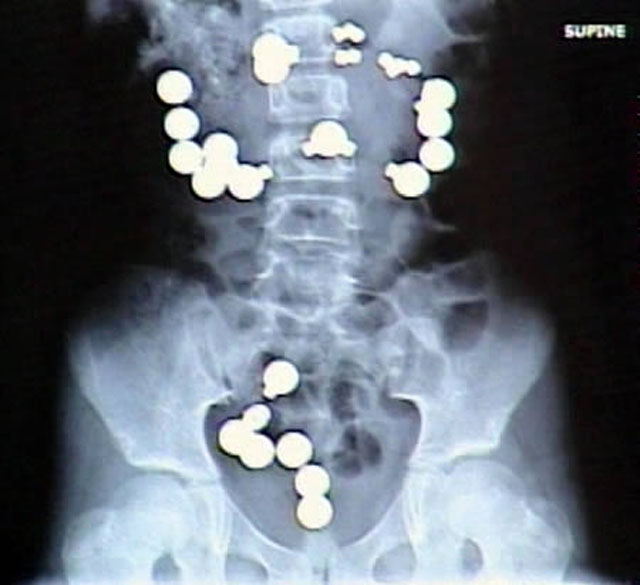

8-year-old Haley Lents of Indiana swallowed 10 magnets and 20 steel balls from a Magnetix toy set. The magnets and balls attracted one another within her digestive tract, ripping a total of eight holes in her intestines and forcing her parents to rush her to the hospital for emergency surgery. Lents later told reporters that the magnets and steel balls "looked like candy"

X-ray revealing a diamond ring inside Wilfredo Gonzalez-Cruz, 30, of Chicago, that he allegedly stole from the home of a women in Cicero, and then swallowed.

This X-ray that shows the quarter that was swallowed by a 6-year-old girl.

52-year-old Dutchwoman Margaret Daalman came to hospital complaining of stomach ache, and one glance at her X-ray shows why.Surgeons in Rotterdam in the Netherlands were astonished when X-rays showed 78 different items of cutlery in her stomach.